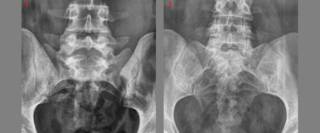

На снимке можно увидеть явные признаки полного или неполного сращения поясничного позвонка L5 с крестцом и крыльями подвздошной кости.

Рис. 2. Типы сакрализации: 1 — неполная двусторонняя; 2 — двусторонняя составная; 3 — двусторонняя костная; 4 — односторонняя суставная; 5 — односторонняя костная; 6 — двусторонняя костно-суставная.

Форма и степень ассимиляции переходного позвонка весьма разнообразны (рис. 1 и 2). Ассимиляция проявляется главным образом в изменении поперечных отростков позвонка. В одних случаях наблюдается только расширение одного или обоих поперечных отростков в последнем поясничном позвонке, в других — выраженные их деформации, характеризующиеся соединением с боковыми массами крестца.

Соединения бывают костные, посредством хряща, соединительной ткани и иногда в виде сустава, что и образует неподвижные и подвижные формы ассимиляций. Первые являются бессимптомными аномалиями, вторые могут осложняться деформирующим артрозом и сопровождаться теми или иными клиническими проявлениями (боли, ограничение подвижности, иногда рецидивирующие радикулиты и люмбоишиальгия).

Среди полных форм переходного позвонка различают костные, суставные и костно-суставные формы. При костных формах поперечные отростки позвонка полностью спаиваются с боковыми массами крестца, при суставных — образуются синхондроз, синартроз и истинный сустав; костно-суставные формы характеризуются синостозом одного из увеличенных поперечных отростков и синхондрозом другого поперечного отростка с боковой массой крестца.

Суставные отростки ассимилированного поясничного позвонка обычно остаются обособленными, не сращенными даже при полном костном слиянии поясничного позвонка с крестцом, что указывает на происхождение I крестцового позвонка при шестипозвонковом крестце из поясничного позвонка. Неполные ассимиляции также бывают двусторонними и односторонними.